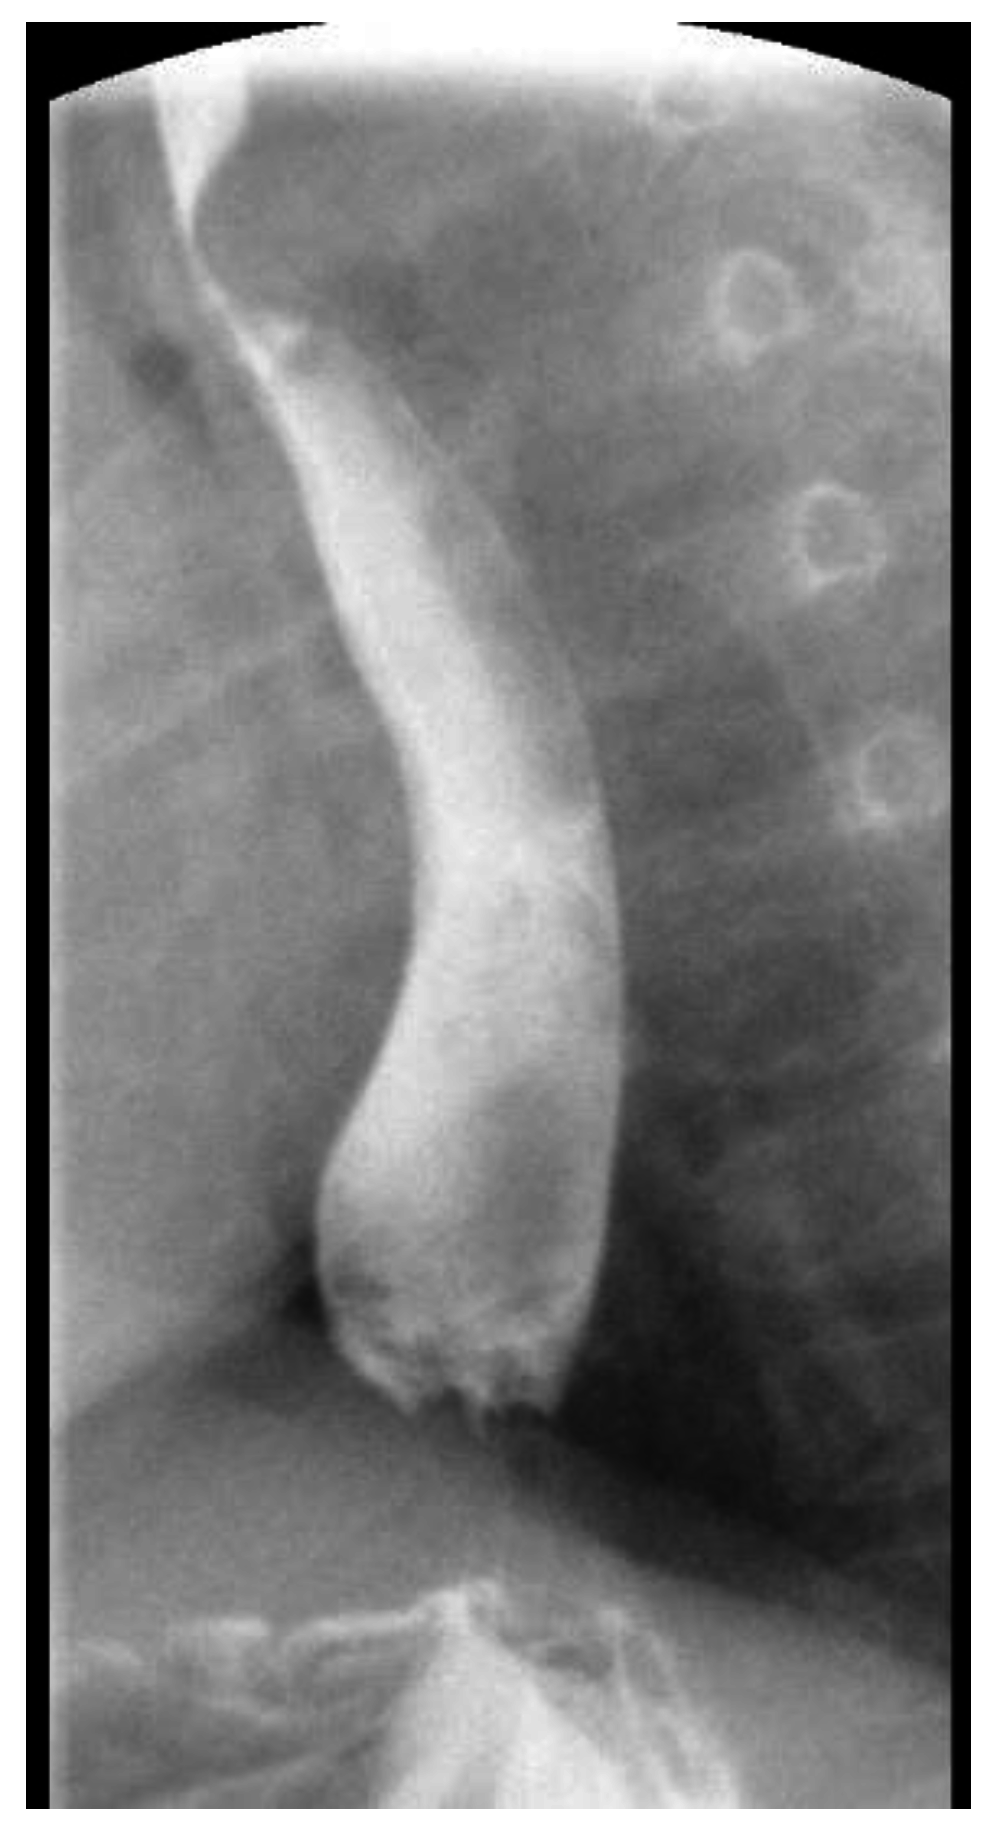

2. Case Report 1